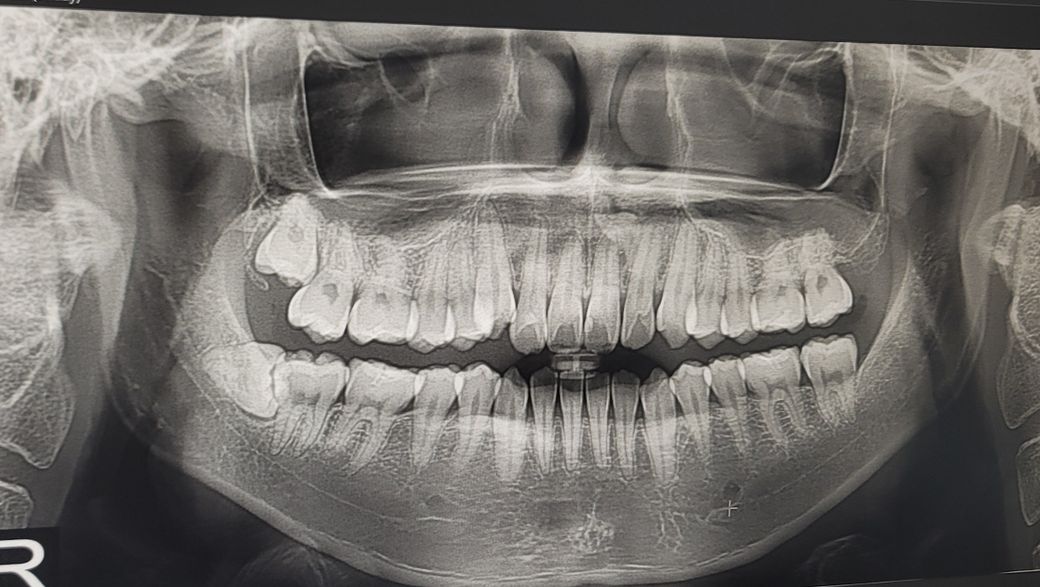

앞니 잇몸 누르면 약한 통증이 느껴집니다

안녕하세요 올해 5월에 12번 치아가 찬 음료를 마실때 굉장히 시리더니

3~4일 후에는 더이상 찬거에는 시리지 않고 24시간 내내 진통제가 없으면 잠을 못잘정도로

아팠습니다 그래서 치과를 3군데 이상 방문하여 엑스레이를 찍고 확인해봤는데

치과의사분들이 모두 x-ray상에서는 이상이 없다

(올해 5월 말에 찍은 사진)

위에 빨간 부분을 누르면 정말 약하게 통증이 있고 운동을 하면 저기서 맥박도 느껴집니다

• 1번 째 사진

• 2번 째 사진

1. 작은 방사선사진을 한번 찍어보시기 바랍니다 큰 방사선사진보다 화질이 좋고 왜곡이 적습니다

2. 큰 방사선사진상 가운데에서 두번째 치아 뿌리끝으로 불투과성 병소로 추정되는 구조가 관찰되나 확실하지는 않고 이로인해 통증이 생겼을지는 확정적이진 않습니다